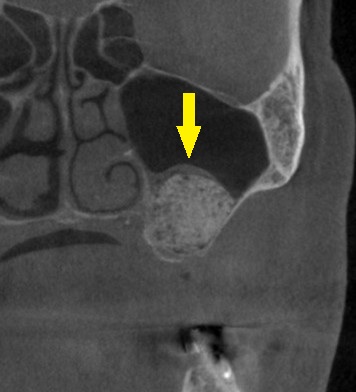

ご了承いただけましたので、本日、左側上顎のサイナスリフトを施行しました。

下の写真下段が手術後のCTです。